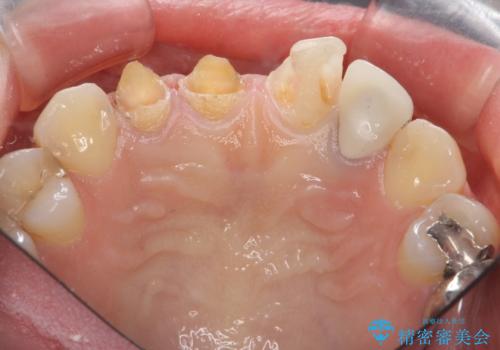

- 前歯を天然の歯のようにきれいにやりかえたいと希望され来院されました。

根尖病変の存在が判明したため、感染根管治療後にオールセラミックジルコニアクラウンを製作します。

- 37万円(仮歯×3・ファイバーコア×2・ジルコニアクラウン×3)費用は治療当時の料金となります